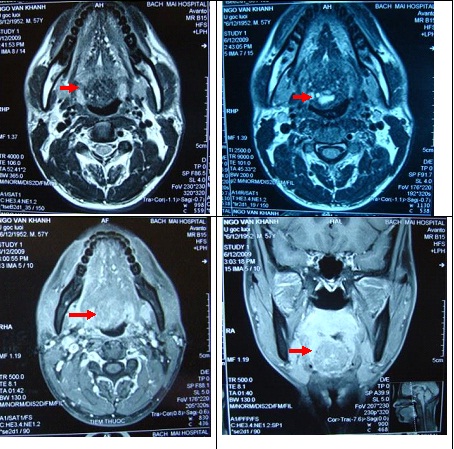

Sau đó bệnh nhân được chụp cộng hưởng từ, xác định chính xác u vùng gốc lưỡi kích thước 15x20 mm (ảnh 2).

Ảnh 2: Kết quả chụp MRI: U vùng gốc lưỡi kích thước 15x20mm, nhưng không khẳng định được bản chất của khối u này